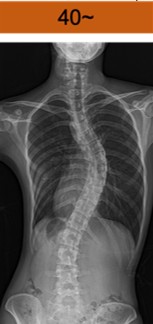

コブ角 40度以上

40°~